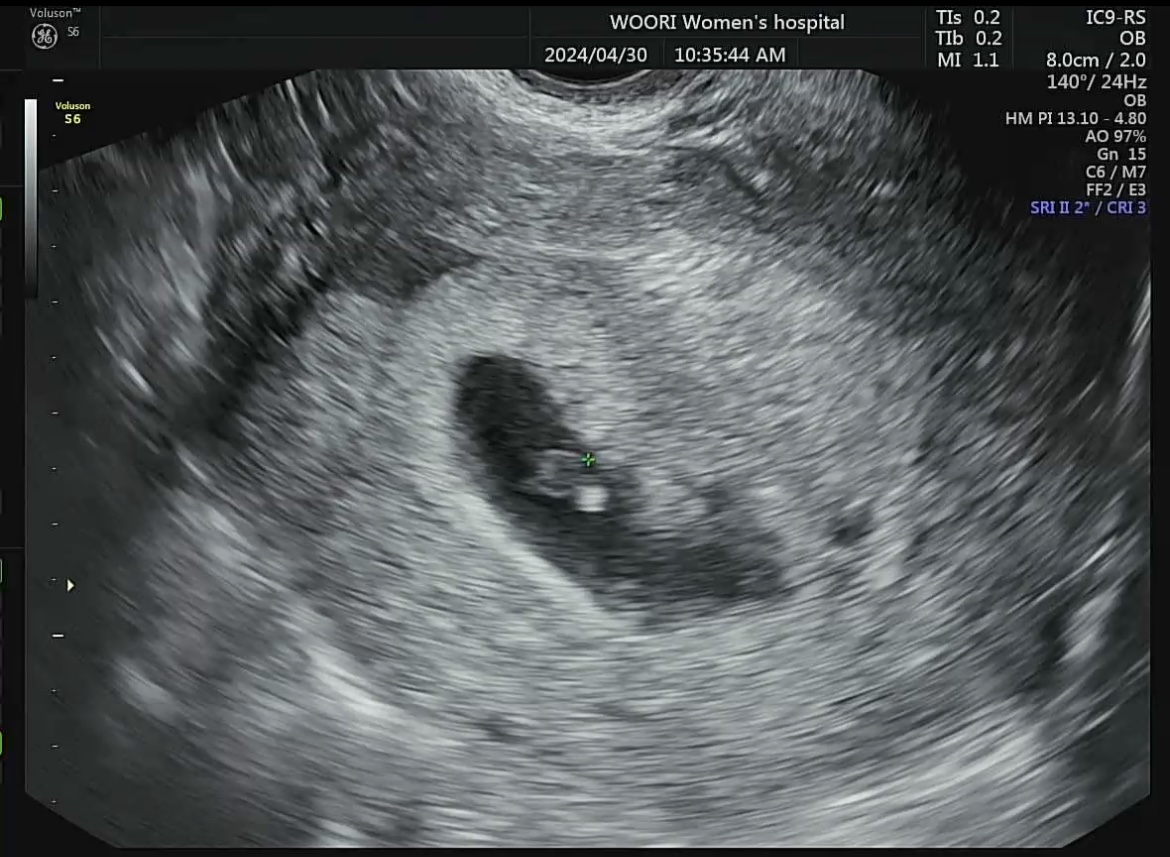

| 4월 30일 | 6주 0일 심장(115bpm) 뛰는 거 확인 | 초음파 | 28,300원 | |